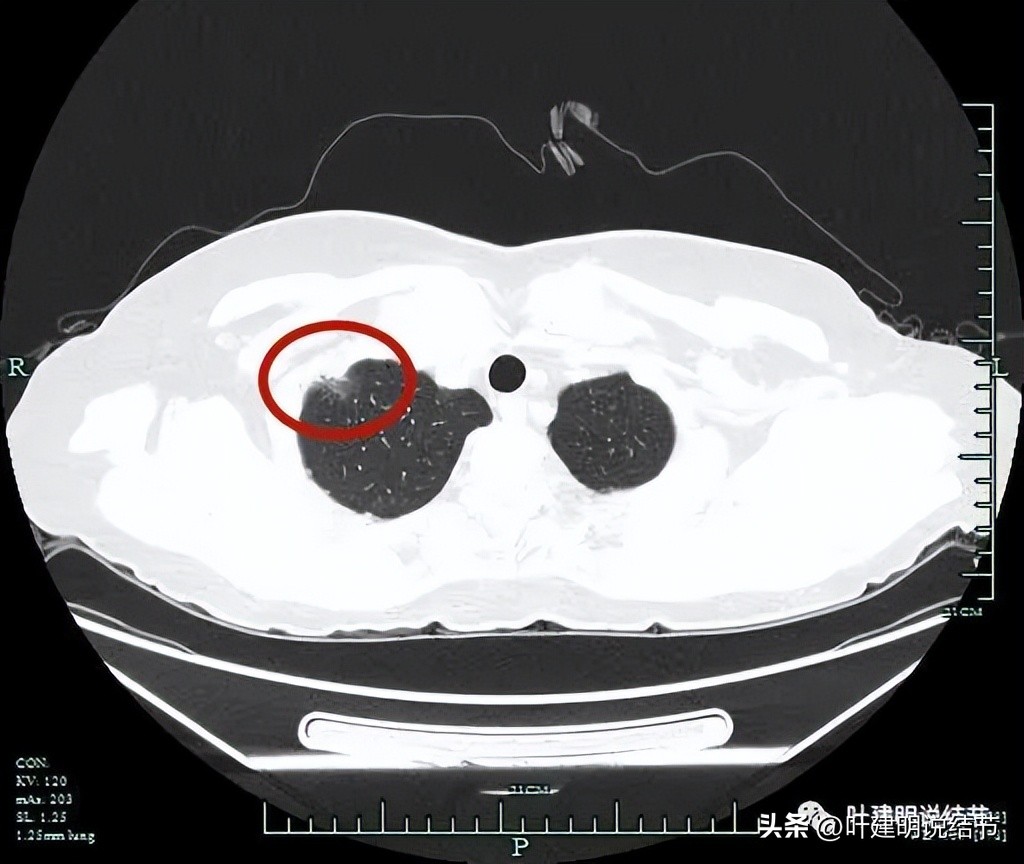

患者某A,女性,今年58岁,约2月前在外院做其他手术时常规检查发现右上叶磨玻璃结节,前些天来门诊看。杭州市肿瘤医院多学科诊疗团队一致认为考虑浸润性腺癌,不能再随访了,得赶紧手术。我们来看看她的影像:

右上叶见磨玻璃密度结节,紧邻胸膜

胸膜侧似乎有偏实性成分